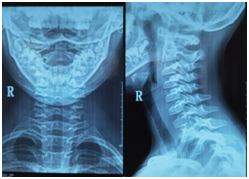

影像:自带当地医院及我院所摄X线片影像均提示寰枢关节半脱位。(左为外院,右为我院)